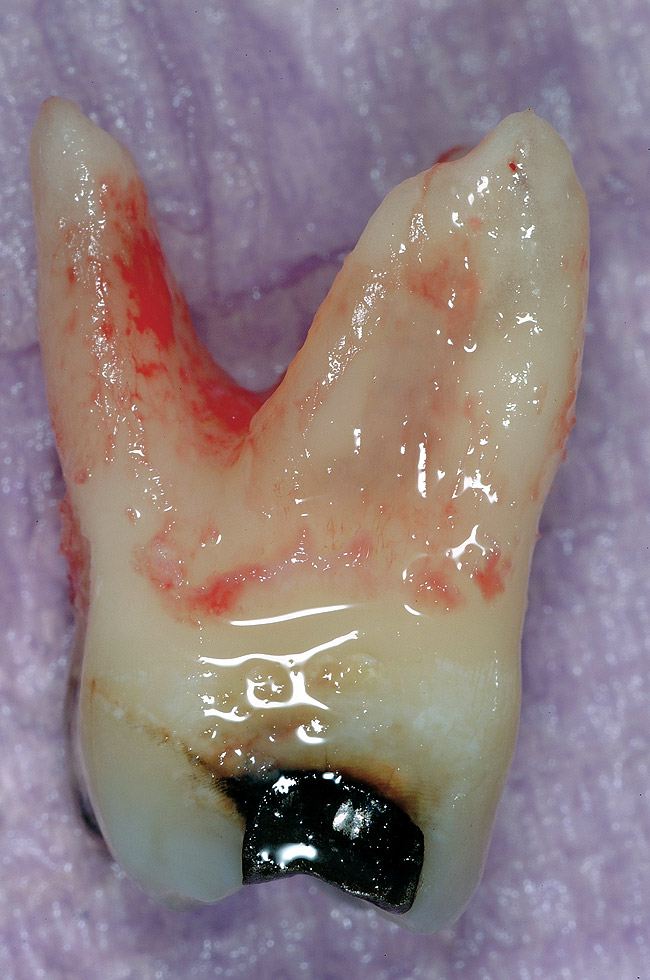

Figure 1 shows a radiograph of a typical maxillary first molar. Upon extraction, the apical anatomy was immediately studied and photographed under a global microscope ( Figure 2, Figure 3, Figure 4, Figure 5 and Figure 6). That is a take-home lesson; the extracted teeth should be studied with loupes or microscopes. These photographs demonstrate an important lesson. The two-dimensional radiograph shows three roots. In reality, however, a significant percentage of maxillary first and third molars—80% in some studies—have four roots and four or more canals. 1,2 While the MB and MP (MB-2) roots are usually fused, their morphology is unique. For diagnostic, access, and shaping purposes, it is safer to think of them as separate roots. Wisdom teeth often exaggerate the anatomic features of first and second molars, and a significant percentage of maxillary third molars have four distinct roots. The author's personal bias is to consider most maxillary first the radiographic apex of the tooth. The use of the radiographic root apex for use as the reference point for measuring the apical extent of the root filling is the common standard, yet has been criticized because of the poor correlation between the location of this point and the actual canal foramen. 5 The illustrations used in advertising and manufacturer's "tip cards" only further the notion of simple foramen anatomy. While simple anatomy is often the case with incisor teeth, a quick perusal of the posterior teeth in Brown and Herbransen's Dental Anatomy & 3D Interactive Tooth Atlas demonstrates that a significant portion of the foramen exit short of the apex and have multiple foramina. 6 The same extracted tooth in Figure 2 demonstrates that the palatal foramen is more than a millimeter short of the radiographic apex. If this tooth were filled to the constriction, which for arguments sake is 0.75 mm from the foramen, a straight-on radiograph would depict the fill as being at least 2 mm "short."